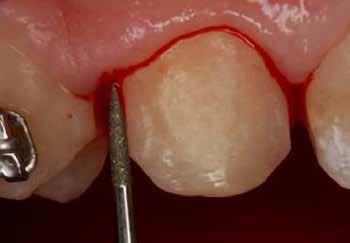

A szemfog megfelelő inklinációjának eléréséhez az oldalsó metsző helyén a palatinális felszínt is el kell csiszolni. Ennek a felületnek nem szabad interferenciát okoznia a harapásban, és lehetővé kell tennie a megfelelő metszőfog-vezetést [14]. A formázás előtt meg kell vizsgálni a szemfog vesztibulo-orális pozícióját. Lapos vesztibuláris felszínnel rendelkező szemfog esetén szükség lehet egy elsőrendű hajlításra a középső metsző és szemfog között (főleg, ha a szemfogon egy oldalsó metsző bracket van, melyben a beépített in-out érték magasabb) annak érdekében, hogy elérjük a megfelelő vesztibulo-orális pozíciót a fognyak szintjén, és elkerüljük a palatinális elcsiszolást (3. a-b ábra), [39].

A zománc elcsiszolásának mértékét az orális és incizális felszínen a harapás határozza meg, ennek vizsgálatához tükröt és artikulációs papírt használunk [36]. Ideálisan, teljes interkuszpidációban a frontális kontakt olyan enyhe, hogy az artikulációs papír kicsúszik, míg propulzióban, metsző fogvezetésnél a jelölésnek a palatinális felszín incizális harmadában kell lennie mind a középső metszőn, mind a szemfogon. A gyémánteszközök legalkalmasabb formája a palatinális elcsiszoláshoz a lándzsa és rögbi alakú (Komet 0640, piros finom lándzsa Rodentica 806314257514020 (max. 300 000 fordulat/perc), rögbi Rodentica 800314278514020 finom piros (27-76 µm) gyorsítóban. Ezt követően könyökdarabba fogott Sof-Lex korongokkal szükséges polírozni (4. a-b. ábra).

3. a–b ábra: .019x.025” acél mint befejező fogszabályozóív vesztibuláris hajlításokkal a 11-13., a 21-23., valamint a 24-25. és a 14-15. fogak között. 4. a-b. ábra: A szemfog palatinális felületének formázása (a, Rodentica 257) és polírozása narancssárga Sof-Lex koronggal (b). A braketeket már eltávolították ezekről a fogakról.